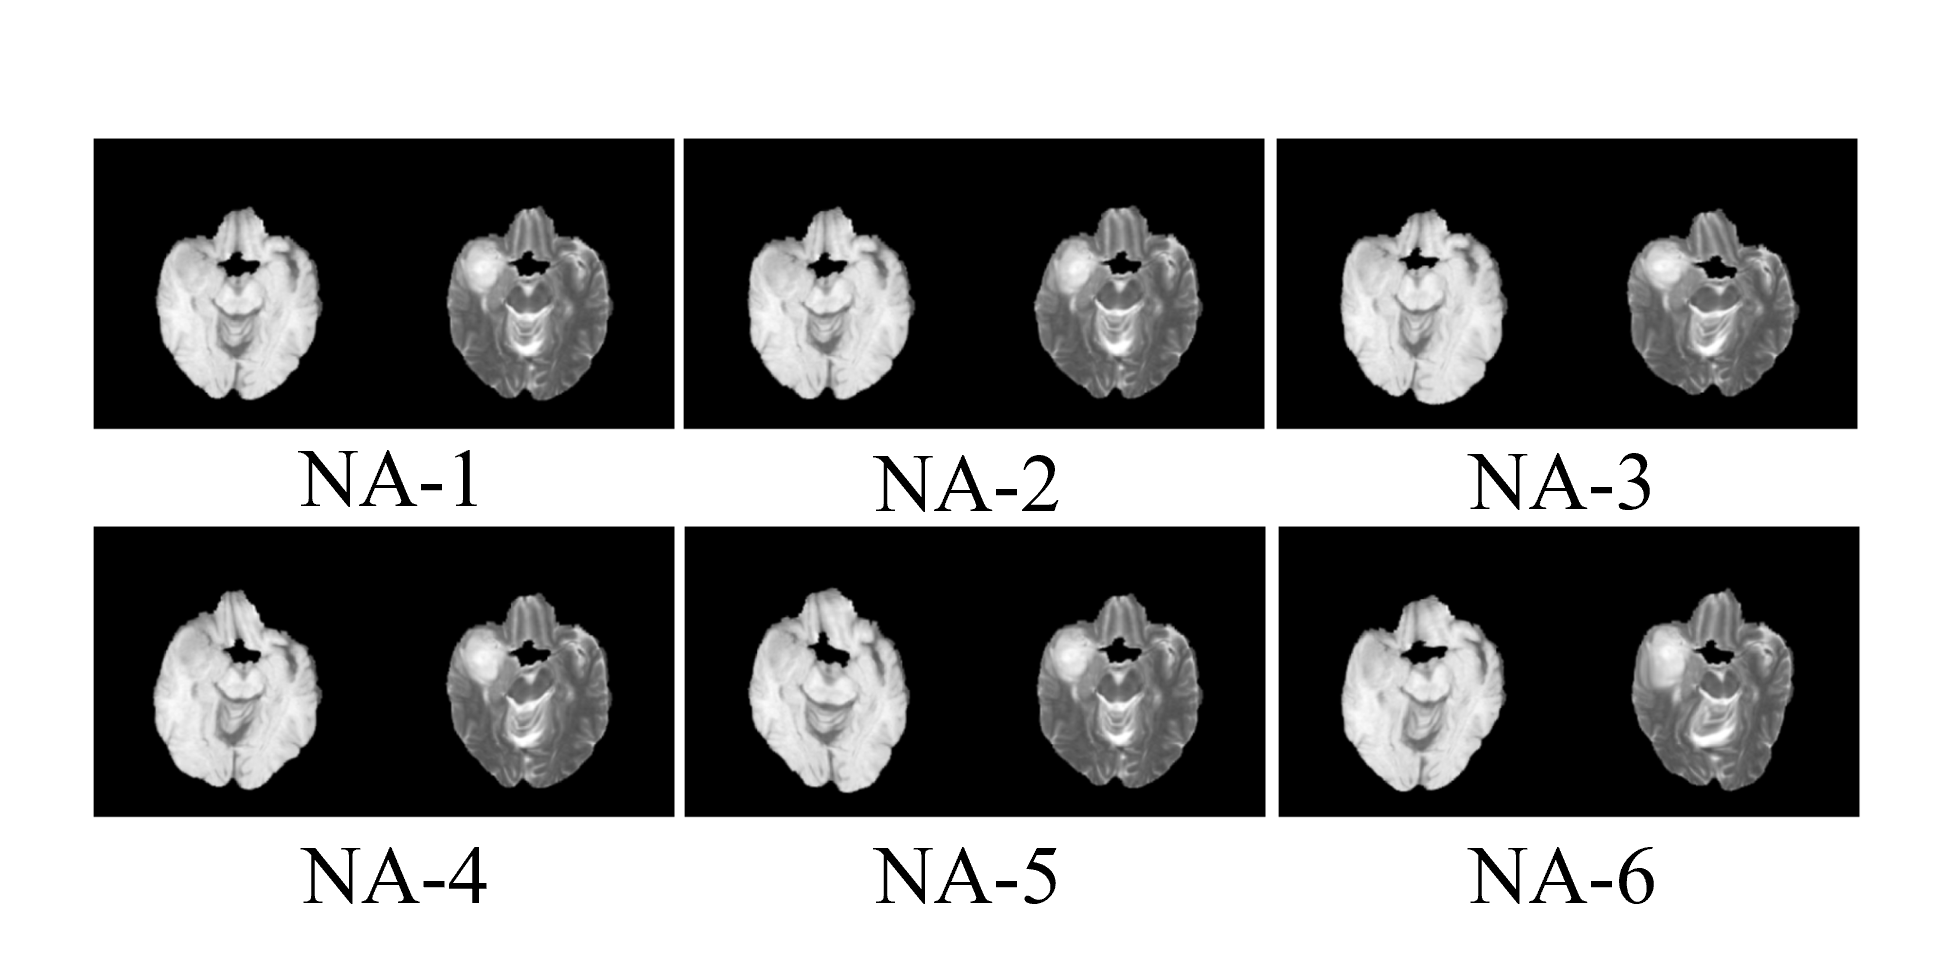

Brain T1-T2 dataset On the brain T1-T2 MRI dataset, we simulated 6 different levels of non-affine misalignments. A visualisation of non-affine misalignment is provided in Figure 5. An overview of implementation parameters for non-affine misalignment is provided in Table 4. More specifically, the non-affine misalignment was simulated using elastic deformation on control points (Rand2DElastic in MONAI library222https://docs.monai.io/en/stable/transforms.html#rand2delastic). The spacing between control points was set to [40, 40], while the magnitude was set to incremental levels from NA-1 to NA-6.

Refer to caption

Figure 5: Example images with different levels of non-affine misalignment.

In simulation experiments on the brain dataset, 6 non-affine deformations were randomly applied on the training sets to simulate the misalignment. The non-affine deformation was implemented with elastic deformation on control points (Rand2DElastic in MONAI library [Cardoso et al.(2022)Cardoso, Li, Brown, Ma, Kerfoot, Wang, Murrey, Myronenko, Zhao, Yang, Nath, He, Xu, Hatamizadeh, Myronenko, Zhu, Liu, Zheng, Tang, Yang, Zephyr, Hashemian, Alle, Darestani, Budd, Modat, Vercauteren, Wang, Li, Hu, Fu, Gorman, Johnson, Genereaux, Erdal, Gupta, Diaz-Pinto, Dourson, Maier-Hein, Jaeger, Baumgartner, Kalpathy-Cramer, Flores, Kirby, Cooper, Roth, Xu, Bericat, Floca, Zhou, Shuaib, Farahani, Maier-Hein, Aylward, Dogra, Ourselin, and Feng]) with 6 incremental levels denoted as NA-1 to NA-6. In real-world experiments on the lung dataset, DA-GAN was compared on 8 state-of-the-art (SOTA) medical synthesis methods, including GAN [Goodfellow et al.(2020)Goodfellow, Pouget-Abadie, Mirza, Xu, Warde-Farley, Ozair, Courville, and Bengio], Pix2pix [Isola et al.(2017)Isola, Zhu, Zhou, and Efros], CycleGAN [Zhu et al.(2017)Zhu, Park, Isola, and Efros], UNIT [Liu et al.(2017)Liu, Breuel, and Kautz], MUNIT [Huang et al.(2018)Huang, Liu, Belongie, and Kautz], NiceGAN [Chen et al.(2020)Chen, Huang, Huang, Sun, and Fang], RegGAN-NC [Kong et al.(2021)Kong, Lian, Huang, Hu, Zhou, et al.], and RegGAN-C [Kong et al.(2021)Kong, Lian, Huang, Hu, Zhou, et al.]. Please find more details in Appendix B.1.